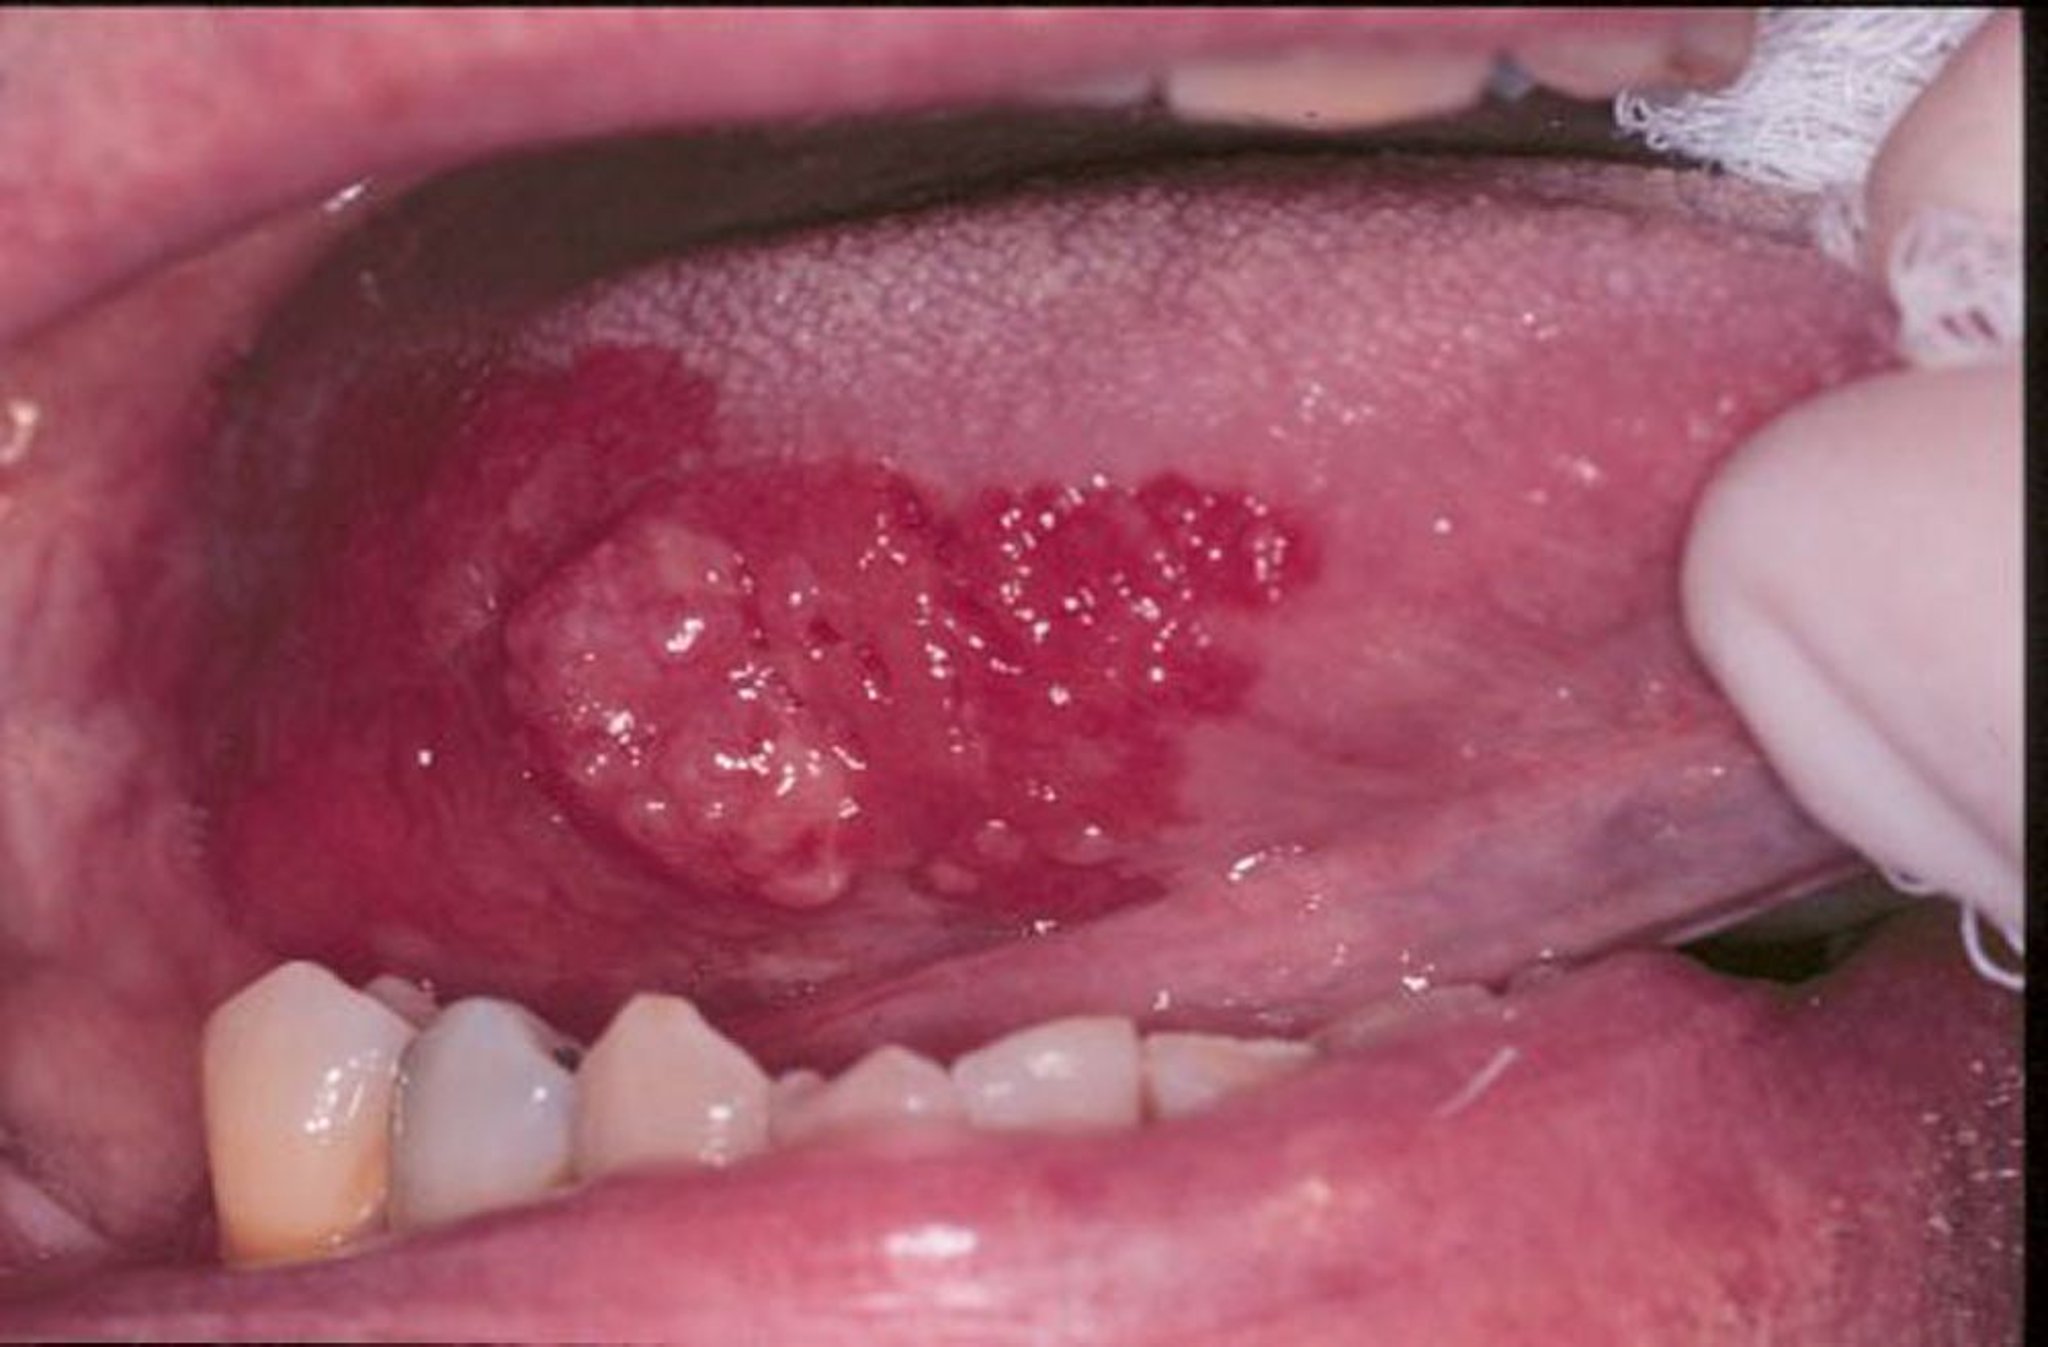

Erythroplakie und Plattenepithelkarzinom

Erythroplakie ist ein allgemeiner Begriff, der rote, flache oder erodierte, samtige Läsionen im Mundbereich beschreiben kann. Auf diesem Bild ist ein exophytisches Plattenepithelkarzinom auf der Zunge von einem Erythroplakiesaum umgeben.

Image provided by Jonathan A. Ship, DMD.